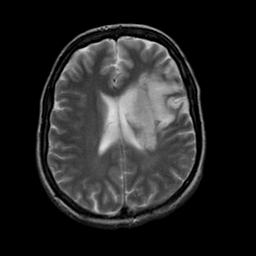

The main limitation of the above-mentioned methods is their dependency on a large number of paired images, i.e., both images belong to the same patient, perfectly registered for training [27], which is difficult to obtain. If the registration has a local mismatch between different modalities, the learning models would generate irrelevant images. To overcome this issue, Zhu et al. [49] proposed cycleGAN to synthesize images from unpaired data in an unsupervised manner. Although cycleGAN has shown remarkable results in reconstructing identical images to the real input, e.g. CT-to-CT, it can not be directly used to synthesize samples from another modality, e.g., MR-to-CT, as there are no direct constraints between real source and synthetic images [39]. For example, Zhang et al. [46] alleviated this issue using an additional loss to force the generated images to be the same as the real ones. Later, SC-cycleGAN [39] defined a structure-consistency loss into the cycleGAN. Specifically, modality-independent neighborhood descriptor (MIND) [9] and a position-based selection strategy is used as structural features and slice selection, respectively. Moreover, several studies conducted bidirectional prediction, i.e., synthesis of CT images from given MR images and vice versa [38, 1]. In addition, many cycleGAN-based methods have been proposed for medical image synthesis from unpaired data [10, 29, 3], but these methods only used the basic discriminator. The basic discriminator only utilizes images in the target domain, while we discovered that using reference images from only the target domain leads to a problem, as shown in Fig. 1 and 2.

In this paper, we propose a bidirectional learning model, known as dual contrast cycleGAN (DC-cycleGAN), for medical image synthesis from unpaired data. Specifically, a dual contrast (DC) loss is formulated that leverages the advantage of samples from the source domain as negative samples to indirectly build constraints between real source and synthetic images via discriminators, and synthesize images more related to the target domain by enforcing the synthetic images to fall far away from the source domain. In addition, structural similarity index (SSIM) [35] and cross-entropy (CE) [48] are integrated into the DC-cycleGAN structure to avoid disappearing gradient information that is caused by a mean absolute error (MAE) and synthesizing irrelevant images. SSIM considers luminance [35] and CE converges fast as its back-propagation error is less than MSE [28]. As can be seen in Figs. 1 and 2, using SSIM and CE with dual contrast can generate more clear and accurate MR images as compared with that of MAE and MSE, and SSIM and CE without dual contrast loss. Although both SSIM and CE with dual contrast and without dual contrast generate similar CT images, SSIM and CE with dual contrast quantitatively generate better images as shown in Table 4. The experimental results indicate that DC-cycleGAN is able to consider more complex features such as structure in synthesizing images and produce remarkable results as compared with other state-of-the-art methods reported in the literature.

Tables 3 and 4 show the results of MR and CT synthesis, respectively. As can be seen, all components play vital role in both tables. SSIM & CE (w) performs significantly better than other losses in synthesizing MR images. This also can be seen visually in Fig. 1. In contrast, SSIM&CE (w) performs slightly better than SSIM&CE (wo) in synthesizing CT images, both generate more or less similar CT images (see Table 4).